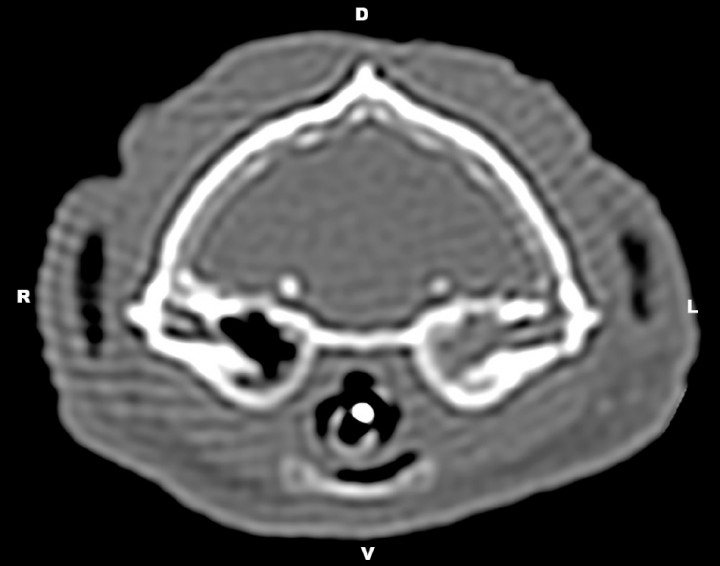

CT of the tympanic bullae was acquired under general anesthesia (GE HiSpeed Dual, GE Heathcare System, Wauwatosa, WI). CT technical parameters were as follows: helical acquisition, bone and standard algorithm, 120 kVp, 200 mAs, 0.6-mm slice thickness, pitch of 0.8, and 0.75 s/rotation. Reformatted images in sagittal and dorsal planes were obtained. The images were reviewed using a picture archiving and computer system (PACS) workstation and bone (window width [WW]= 2000, window level [WL]= 800) and soft tissue (WW=360, WL=60) window display settings. CT examination revealed an accumulation of soft-tissue dense material (65 Hounsfield Units) within the left tympanic cavity and the horizontal portion of the left external ear canal (Fig. 1). Mild sclerosis of the wall of the left bulla was noted (Fig. 2). These findings were consistent with left otitis media and externa.

<p>Transverse computed tomography image at the level of the tympanic bullae using bone window (WW= 2000, WL= 800). Accumulation of soft-tissue dense material within the left tympanic cavity as well as mild sclerosis of the left tympanic wall were observed. R= right, L=left, D=dorsal, V=ventral.</p>

Transverse computed tomography image at the level of the tympanic bullae using bone window (WW= 2000, WL= 800). Accumulation of soft-tissue dense material within the left tympanic cavity as well as mild sclerosis of the left tympanic wall were observed. R= right, L=left, D=dorsal, V=ventral.